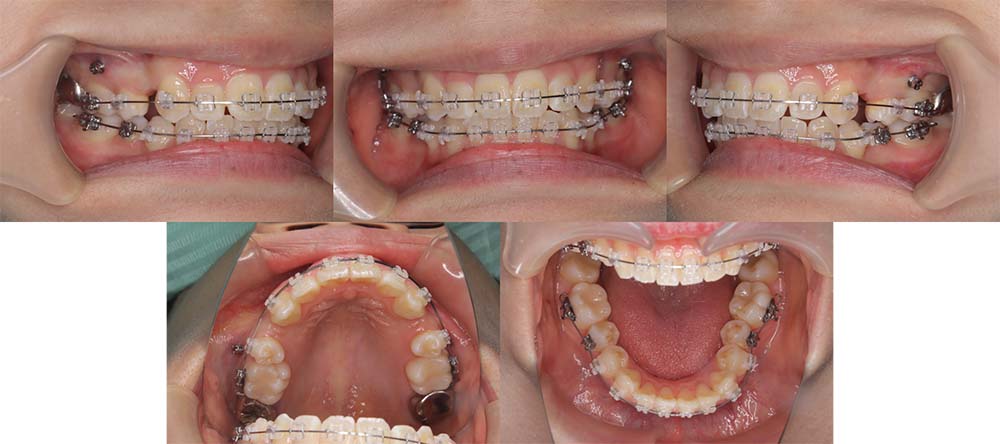

| 症例分類 | 叢生 |

| 診断名 | 上下叢生 |

| 主訴 | 八重歯と下の歯のガタガタが気になる |

| 年齢 | 24歳4ヶ月 |

| 性別 | 女性 |

| 抜歯部位 | 上下左右の第一小臼歯(4本) |

| 使用装置 | 上は裏側、下は表側のワイヤー装置 |

| 治療期間 | 2年8ヶ月 |

| 保定装置 | 固定式保定装置、取り外し式保定装置(8時間) |

| 費用 |

[検査・診断料] ¥49,500 [基本施術料] ¥1,056,000 [調整料] ¥5,500/回 [抜歯] ¥5,500/本 [保定装置] ¥55,000(税込) 抜歯や虫歯治療は他院にて費用が別途かかります。(抜歯¥4,000〜10,000/本)

上下叢生のため、上下第一小臼歯を抜去して上裏側下表側のハーフリンガルで治療しました。

顎間ゴムは治療期間の半年程度使用しましたが、協力度が良好だったためしっかり咬合することができました。

治療開始前にホワイトニングをしたこと、咬合力が強いためか装置の脱離が多く、予定より治療期間が伸びてはしまいました。